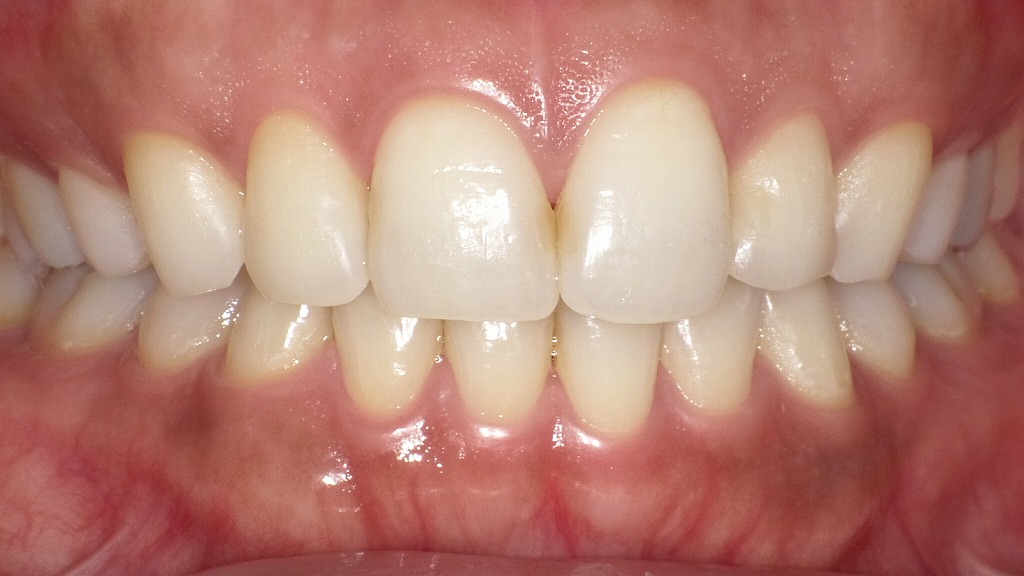

抜歯矯正後の正面観

この画像は、抜歯矯正後の正面観を示しています。全体として非常にバランスの取れた歯列で、以下のような特徴が見られます。

🦷 歯列と咬合の特徴

- 上下の正中(中央ライン)が一致しており、左右対称性が良好です。

- 上下の歯の咬み合わせが自然で、過度な深い咬みや開咬は認められません。

- 上顎前歯の歯軸が適切に傾斜しており、スマイルラインに沿って調和しています。

✨ 審美的な評価

- 歯の形態・大きさ・位置の調和が取れており、自然で美しい印象。

- 歯肉のラインも健康的で、歯と歯肉の境界が滑らかです。

- 歯の色調が均一で、自然な明るさを保っています。